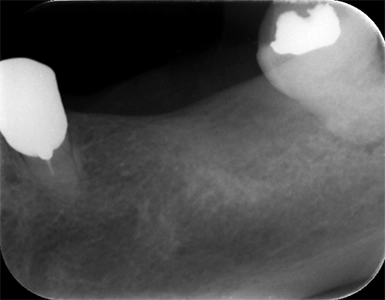

抜歯窩保存術 インプラント埋入術

初診時

左下7抜歯時

骨造成4か月後

インプラント手術後

年齢・性別 55歳・女性

主訴 左下の奥歯より嫌な匂いがする

診断名 左下第二大臼歯 歯根破折、慢性根尖性歯周炎

治療内容 左下7の歯根破折に起因する慢性根尖性歯周炎により抜歯が必要となった。患者様は機能性と審美性の回復を強く希望したため、抜歯後骨造成を行いインプラント治療を行った。

(GBR:歯根破折の炎症により、抜歯窩周囲の骨吸収が進んでおりこの状態ではインプラントを安定して埋入するだけの十分な骨量がないと判断し、GBR(骨造成)を行った。)

インプラント体と骨が強固に結合するまで通常3~6か月の治癒期間を設るため、インプラント体を埋入し、3か月経過後骨との結合を確認した後、型取りを行い仮歯で問題ないことを確認し、セラミックの人工歯(上部構造)を装着して治療完了した。

治療期間 インプラント埋入前に中断があったため1年7か月→初診からインプラント治療完了まで

費用 骨造成:110,000円

インプラント2本:902,000円(1本の場合は544,500円)

リスク・副作用 術後の痛み、腫れ、出血が出ることがある

感染の可能性、腫れや再生不良が起こることがある

喫煙や清掃不良、炎症が重度の場合は組織再生の効果が十分得られないことがある